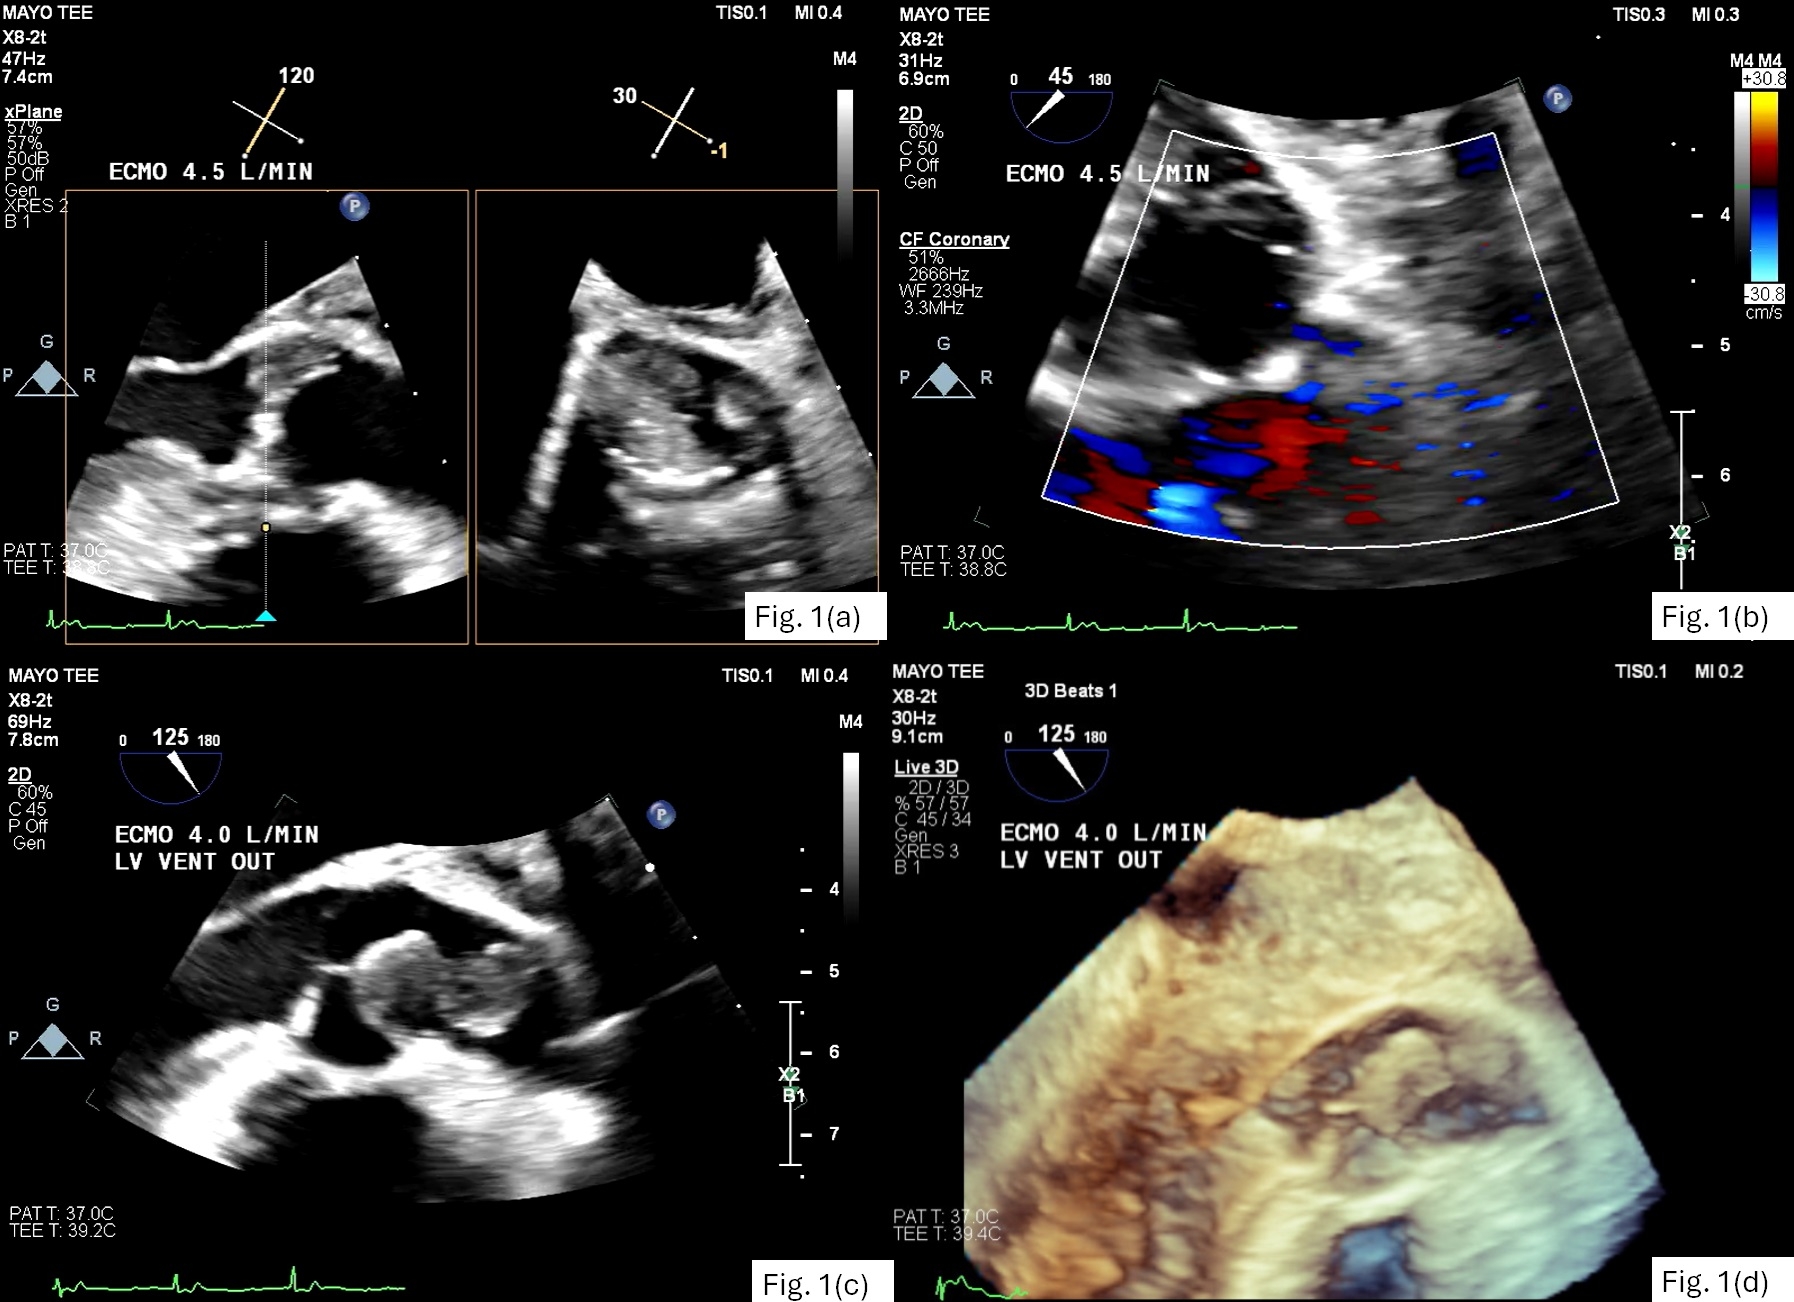

This patient subsequently underwent transcatheter thrombectomy and aspiration of the aortic root with cerebral protection device. Coronary angiogram confirmed proximal RCA occlusion (Fig. 3). Attempts to remove RCA thrombus were only partially successful. She eventually required a second heart transplant due to RV infarction.